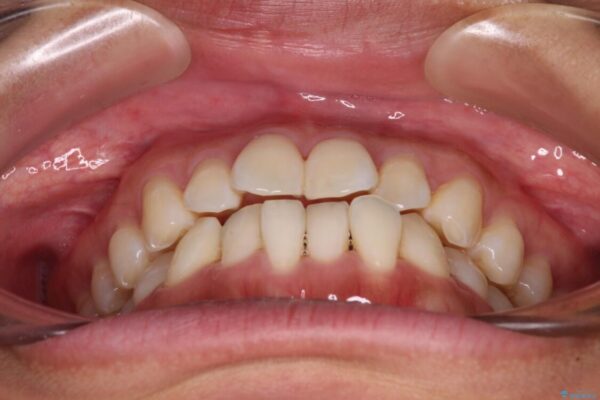

前歯のデコボコで前方に出ていることを気にして来院された患者様です。

上顎前歯が捻れて前方に飛び出しており、下顎前歯もそれに沿うようにデコボコとなっていました。

IPR(歯と歯の間を削る処置)によりスペースを獲得して上下顎前歯のデコボコを改善し、飛び出している前歯が引っ込むように設定し、インビザラインにて矯正治療を行うこととしました。

• 【モニター】前歯のデコボコをインビザラインで改善 治療前画像